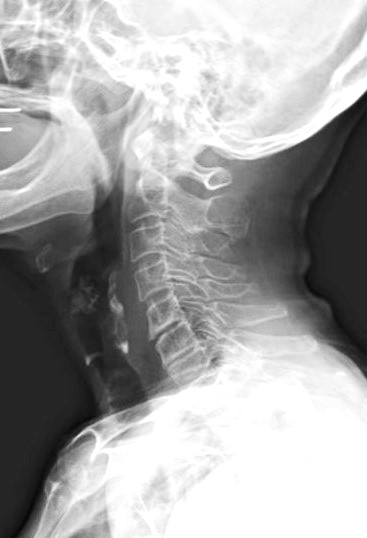

継続使用による変化の一例

ネックオアシスを継続使用した方の頸椎X線写真です。

使用前後で姿勢に変化が見られることがあります。

(※これは一例であり、すべての方に同様の変化が見られるわけではありません)

症例A 6か月使用後 50代女性・デスクワーク